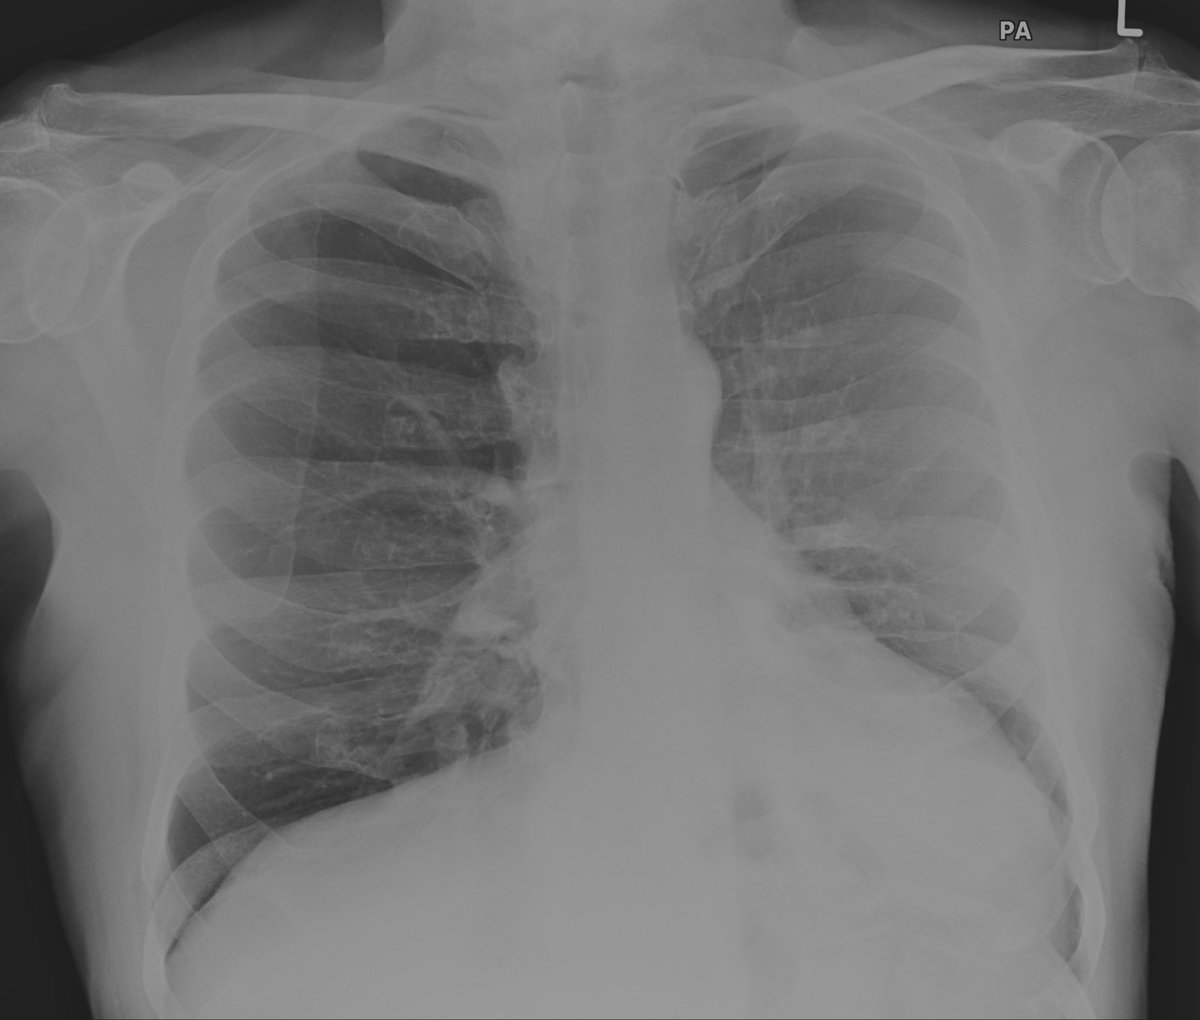

Friday conundrum. Routine chest radiograph and subsequent CT Thorax. Can you see anything abnormal on these images? Can you put it all together? Answers tomorrow.

#FOAMrad#FOAMed#FRCR#radiology#radiologists#CardioEd#cardiotwitter#RadRes#RadReg#meded Have a good weekend! pic.twitter.com/bkLPj1BPTa